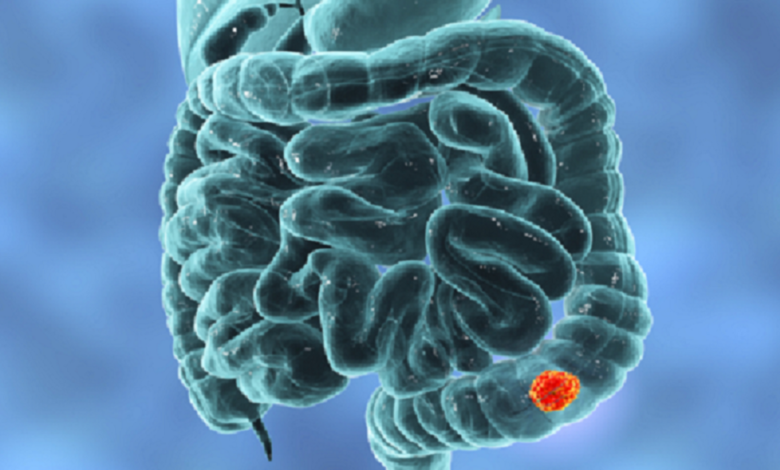

طريقة لتقليل خطر الإصابة بسرطان القولون

وتشير مجلة BMC Medicine، إلى أن تناول الخضروات والحبوب (القمح والحنطة السوداء والشوفان والأرز) والفواكه، يخفض كثيرا من خطر الإصابة بأمراض القلب والأوعية الدموية وارتفاع مستوى ضغط الدم وغير ذلك.كما أن تناول الخضروات والفواكه بصورة منتظمة يمكن أن يخفض خطر الإصابة ببعض أنواع السرطان.

وأن النظام الغذائي الغني بالخضروات والفواكه والحبوب الكاملة (القمح والشوفان) والبقوليات والمكسرات والبذور، يخفض من خطر الإصابة بسرطان القولون لدى الرجال بنسبة 22 بالمئة.

وتستند هذه الدراسة على الملاحظة، ما يعني أن الباحثين لا يعلمون بالضبط لماذا ترتبط بعض المواد بتحسن الحالة الصحية للأمعاء، مع أن لديهم فرضيات عديدة. فمثلا المواد الغذائية النباتية الغنية بمضادات الأكسدة، قادرة على كبح الالتهاب المزمن، وتخفيض خطر الإصابة بسرطان القولون. ولكن مضادات الأكسدة هي مواد غدارة، حيث أن ارتفاع نسبتها في النظام الغذائي، يؤدي أحيانا إلى تطور أمراض السرطان.

وكشفت نتائج دراسات سابقة مكرسة لدراسة تأثير النظام الغذائي وجود اختلافات بين الرجال والنساء من حيث الإصابة بالسرطان. فمثلا كشفت الدراسة التي أجراها البنك الحيوي البريطاني، أن الرجال الذين يتناولون القليل من اللحوم نسبيا، هم أقل عرضة للإصابة بسرطان القولون بنسبة 9 بالمئة، في حين هذا التأثير لم يلاحظ بين النساء.